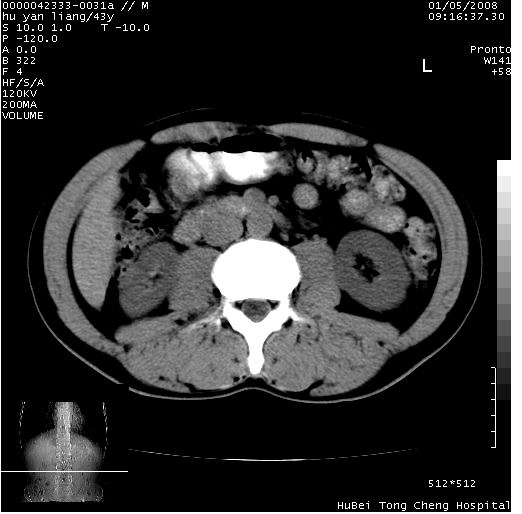

患者 男,43岁。右上腹不适1年余。既往有“肝右叶肝脓肿”病史,经保守治疗后痊愈。

b超提示:1)肝右叶肝内胆管结石。2)肝右叶占位性病变待排。

上中腹部ct轴位平扫+增强扫描(层厚10mm,螺距1.0,重建间隔10mm),图像如下:

肝右上叶偏后方较大团片状钙化灶,支持:肝脓肿后遗改变!